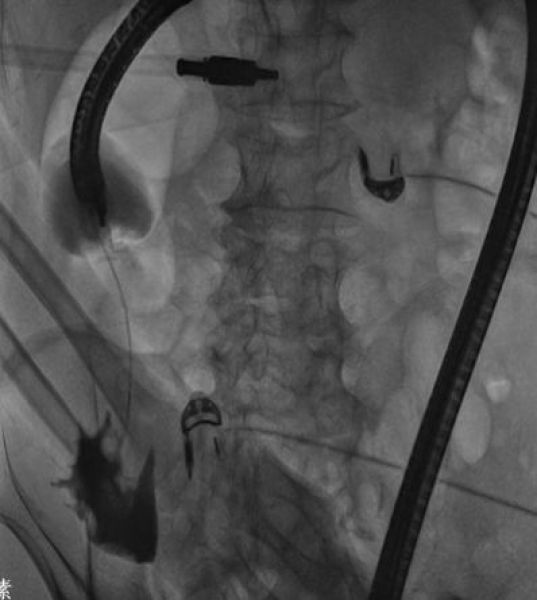

85岁张大爷,因腹痛、呕吐、肛门停止排便10余天拟肠梗阻收住消化一科,腹部CT提示升结肠癌并梗阻,肠镜见升结肠肿物,活检为中分化腺癌。患者高龄,一般情况差,不能耐受外科手术,大活人真要让屎憋死吗?消化内科、普外科讨论后于4月25日在介入室成功置入肠道支架,支架置入后,患者排气排便恢复,呕吐症状缓解,已进食半流质。

肠镜见升结肠肿瘤 造影见升结肠狭窄

成功置入肠道支架